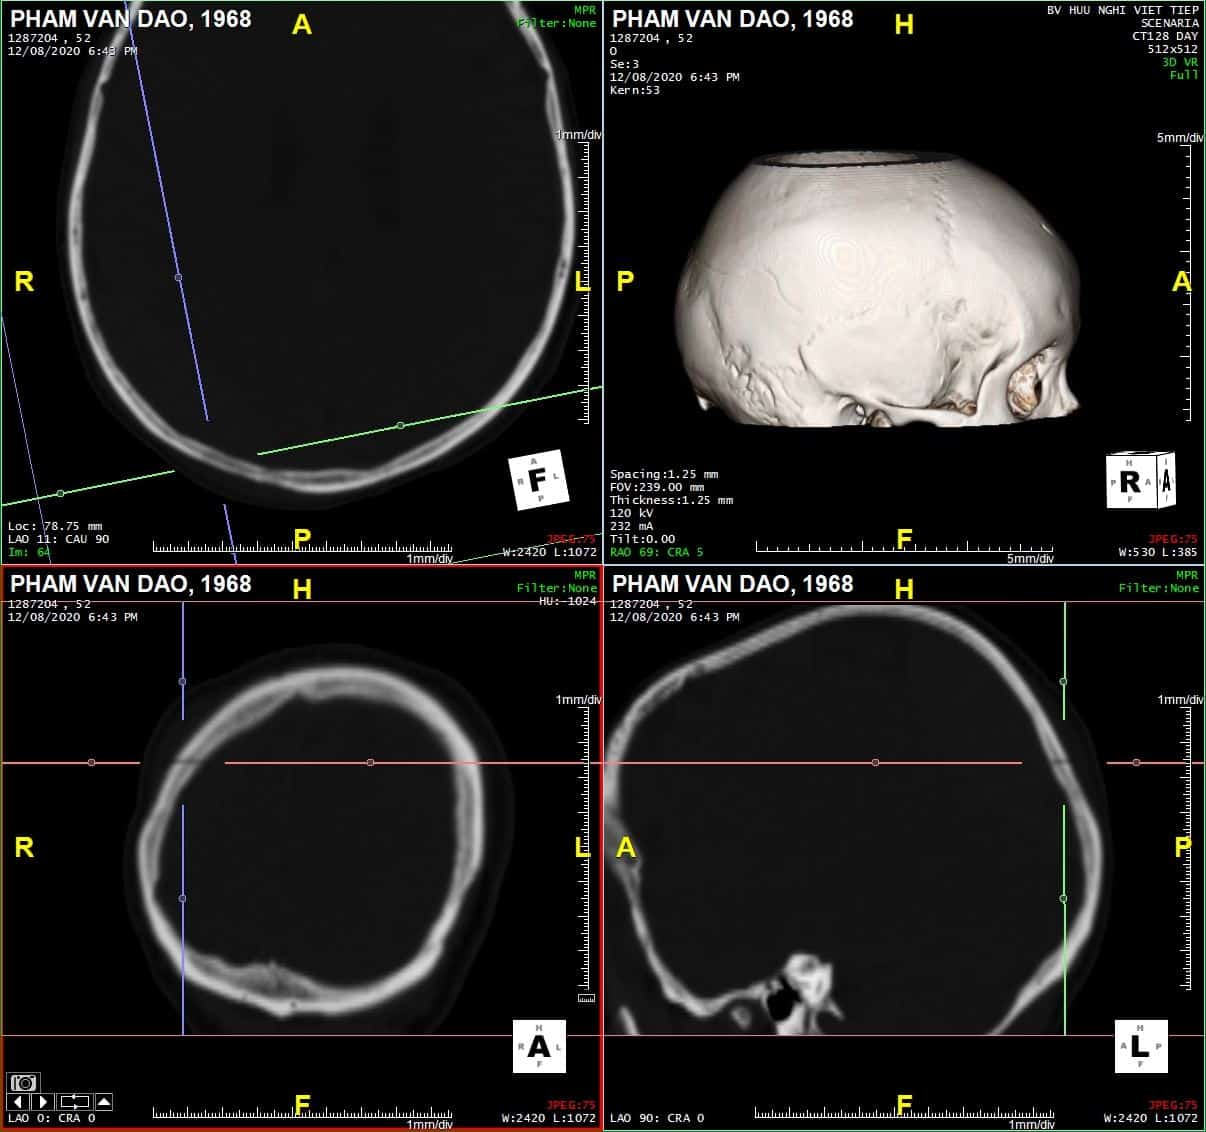

Chấn thương sọ - Ảnh 2

Coronal

# Tụ máu ngoài màng cứng vùng chẩm phải / Vỡ xương chẩm phải: đường vỡ thẳng (Linear fracture) không thấy rõ trên hướng cắt Axial => quan sát rõ trên hướng cắt Coronal và Sagittal.